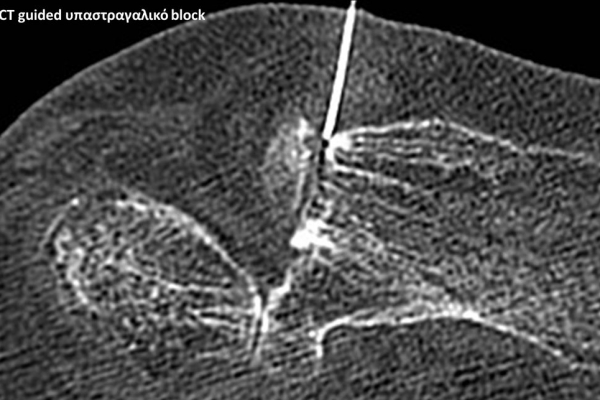

Με την βοήθεια της επεμβατικής ακτινολογίας είναι δυνατόν να πραγματοποιηθούν διαφορες ενέσιμες τεχνικές που αποσκοπούν στη μείωση του μυοσκελετικού πόνου, την ενίσχυση της αποτελεσματικότητας της φυσιοθεραπείας και την επιτάχυνση της διαδικασίας επούλωσης. Οι τεχνικές αυτές περιλαμβάνουν την κατευθυνόμενη έγχυση φαρμάκων ή πραγματοποίηση θεραπευτικών χειρισμών ακριβώς στη θέση τηςπαθολογία. Ετσι εξασφαλιζεται η μέγιστη αποτελεσματικότητα ( έως 95% κατά περίπτωση) και ασφάλεια σε σχέση με τυφλούς χειρισμούς χωρίς ακτινολογική καθοδήγηση.